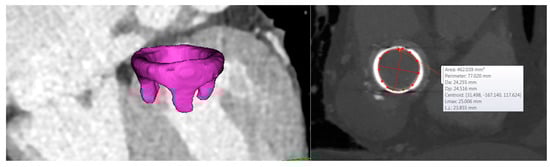

Figure 2.

3D segmentation of the bioprosthetic heart valve and dimension of the mitral valve annulus.